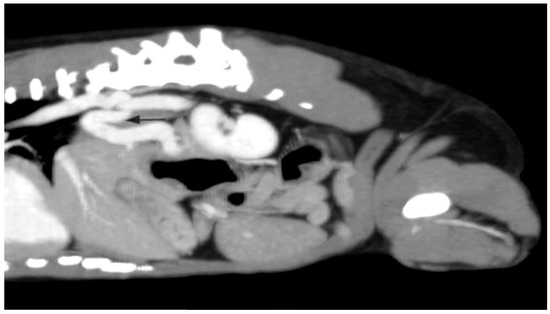

2.3. Case C (Dog)

2.4. Case D (Dog)

2.5. Case E (Cat)